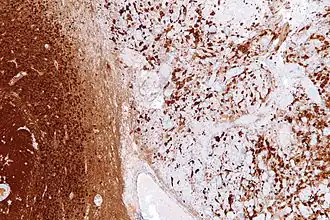

Reactive astrogliosis is the most common form of gliosis and involves the proliferation of astrocytes, a type of glial cell responsible for maintaining extracellular ion and neurotransmitter concentrations, modulating synapse function, and forming the blood–brain barrier.[3] Like other forms of gliosis, astrogliosis accompanies traumatic brain injury as well as many neuropathologies, ranging from amyotrophic lateral sclerosis to fatal familial insomnia. Although the mechanisms which lead to astrogliosis are not fully understood, neuronal injury is well understood to cause astrocyte proliferation, and astrogliosis has long been used as an index for neuronal damage.[4] Traditionally, astrogliosis has been defined as an increase in intermediate filaments and cellular hypertrophy as well as an increase in the proliferation of astrocytes. Although this hypertrophy and proliferation in their extreme form are most closely associated with the formation of a glial scar, astrogliosis is not an all-or-none process in which a glial scar forms. In fact, it is a spectrum of changes that occur based on the type and severity of central nervous system (CNS) injury or disease triggering the event.[5] Changes in astrocyte function or morphology which occur during astrogliosis may range from minor hypertrophy to major hypertrophy, domain overlap, and ultimately, glial scar formation.[5] The severity of astrogliosis is classically determined by the level of expression of glial fibrillary acidic protein (GFAP) and vimentin, both of which are upregulated with the proliferation of active astrocytes.[4][6]